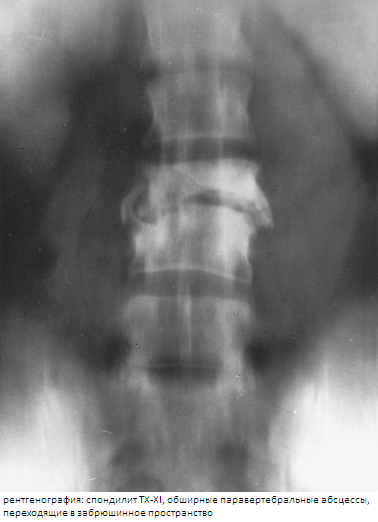

Инфильтрация в позвоночном канале выявлялось у 45(32,1 %) больных. На рентгенограммах абсцессы хорошо выявлялись в грудном отделе позвоночника, где они видны на фоне воздушной легочной ткани. Забрюшинные абсцессы выявлялись по косвенному признаку расширения контуров m.iliopsoas major, когда достигали значительных размеров. Невозможно было увидеть абсцесс мягких тканей спины и небольшие паравертебральные абсцессы в поясничном отделе позвоночника. Контуры абсцессов и их соотношения с окружающими органами на рентгенограммах и томограммах удавалось определить не всегда. КТ и МРТ в равной степени хорошо выявляли абсцессы, их камеры, соотношения с позвонками и окружающими органами и тканями, особенно после внутреннего контрастирования. На ранней стадии формирования абсцесса отмечалась инфильтрация жировой прослойки вокруг тела позвонка. Преимущество МРТ — возможность многопроекционного исследования, что позволяло выявить соотношения абсцессов не только с окружающими тканями, но и связь их между собой. Комплексная оценка изменений костной структуры, выявляемых на рентгенотомограммах и КТ, и патологических изменений сигнала на МРТ, давала представление о морфологических изменениях в позвоночнике и о фазе туберкулезного спондилита.

Наличие паравертебральных абсцессов, на фоне выраженной интоксикации и нарушение функции паренхиматозных органов усиливает деструкцию костной ткани, которые встречались достоверно чаще среди больных 1-й группы (88,3 %), чем 2-й группы (66,6 %). Свищевые формы процесса наблюдались у 8,1 % больных 1-й группы и у 3,7 % больных 2-й группы.